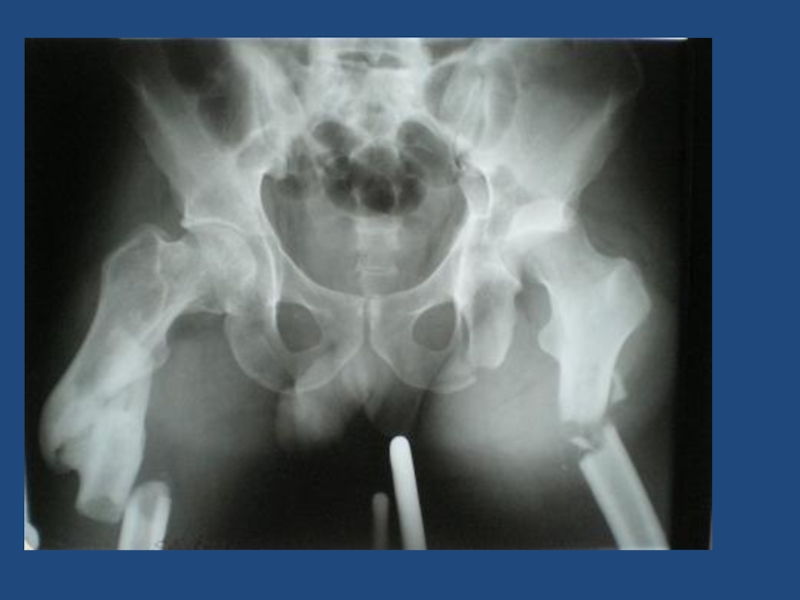

Разрыв симфиза,